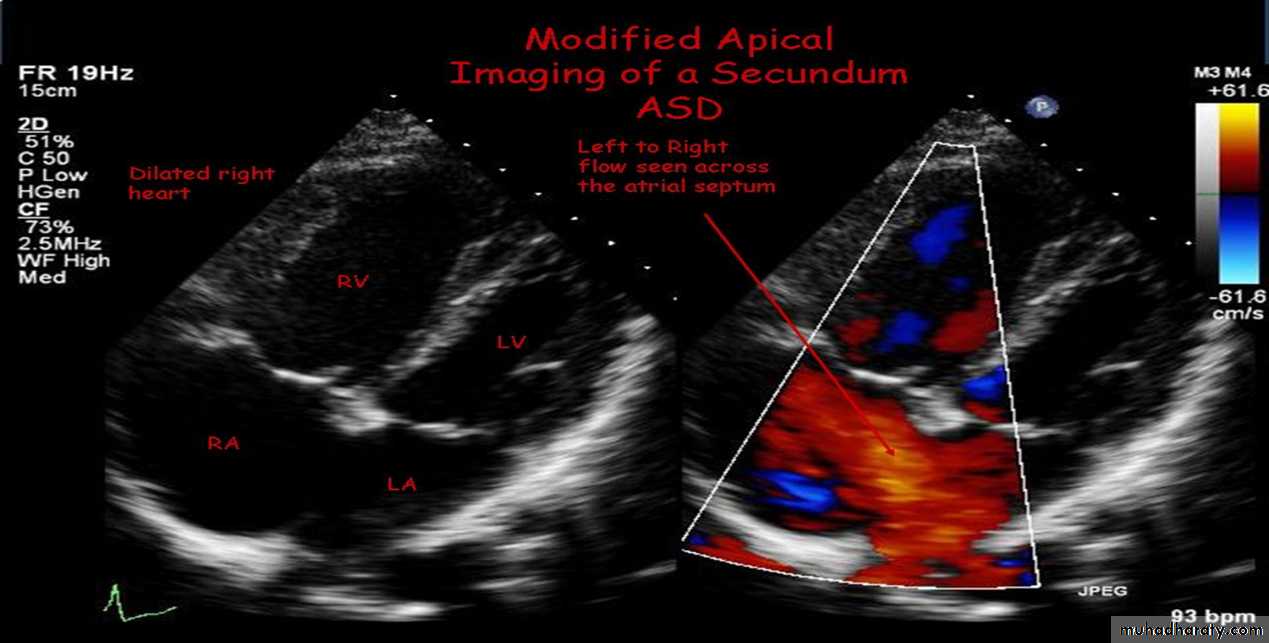

1- Ostium secundum defect is the most common type of ASD, accounting for 50% to 70% of all ASDs. This defect is present at the site of fossa ovalis, allowing left-to-right shunting of blood from the left atrium to the right atrium

3-Echocardiography

The location and size of the atrial defect are readily appreciated by two-dimensional scanning . The shunt is confirmed by pulsed and color flow Doppler .